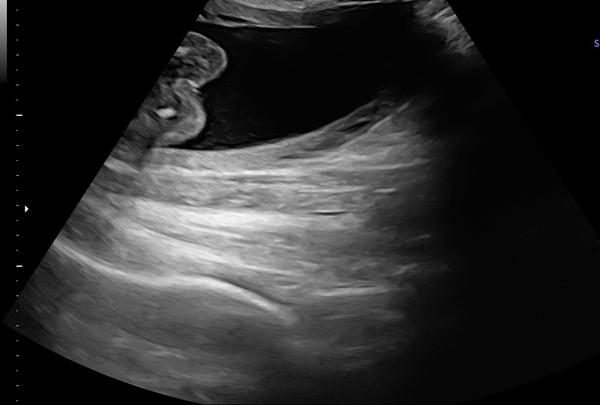

Aké pohlavie dieťatka vidíte na fotke z ultrazvuku?